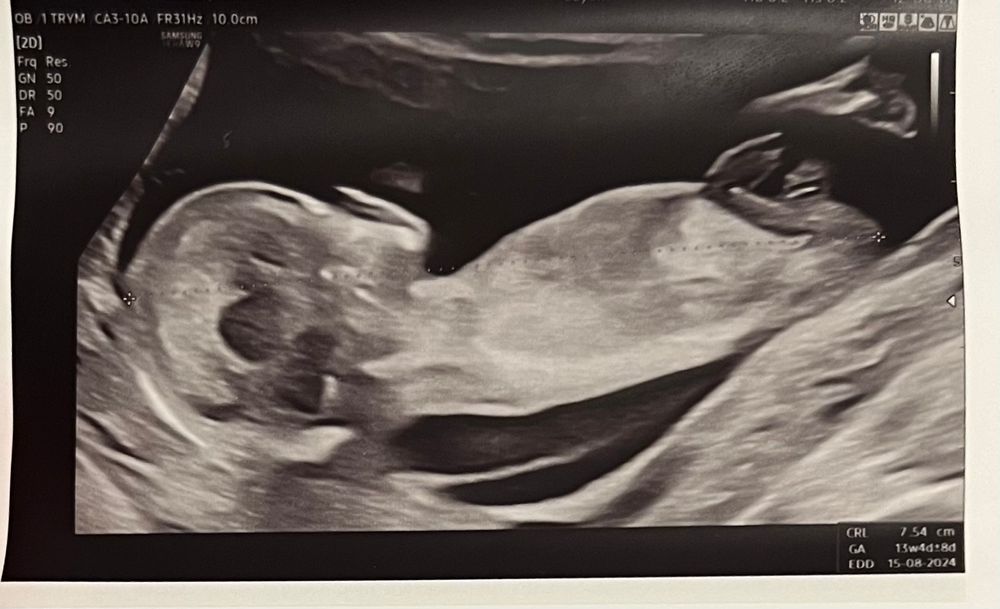

fight flight, мне сказали подождать второго скрининга (19 недель) чтобы видеть точно кто там)

Карина, так долго... Может врач молодой? У меня гиня на 12 все поняла. На 14 сказала точно

fight flight, мне тоже на первом скрининге сразу сказали кто будет , так как узист опытный

fight flight, я думаю зависит от опытности врача и качества его аппарата. По ОМС на первом скрининге мне не сказали пол, сказали на промежуточном УЗИ в 17-18 недель только. А вот платно уже на 11 неделях врач сказал и сказал правильно.